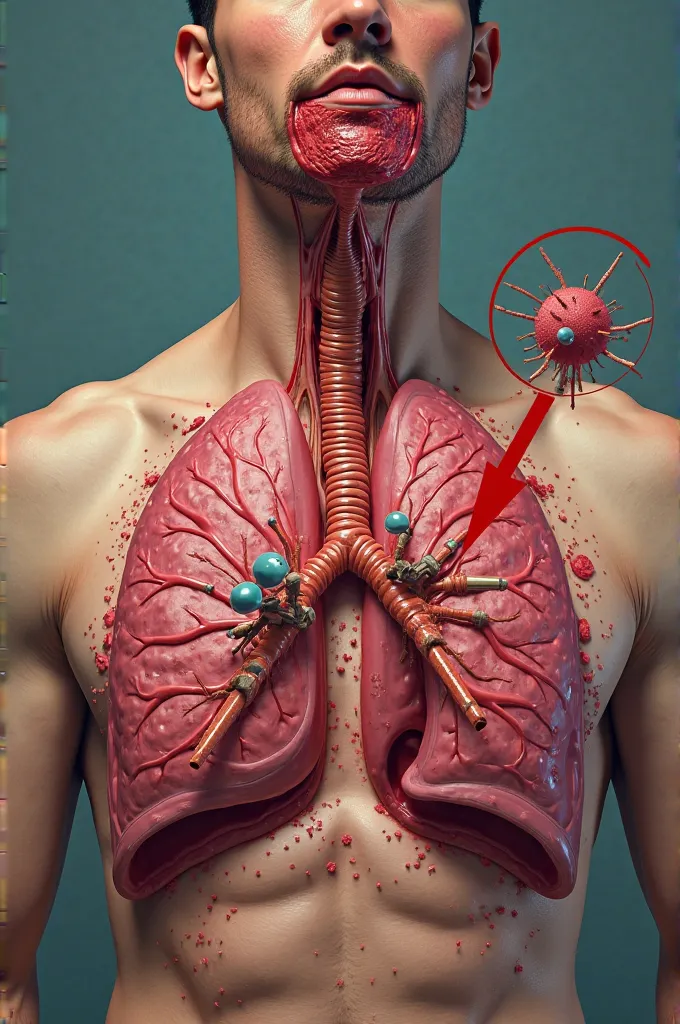

Generate a lungs, the right side lungs is healthy vibrant color surrounded with

Generate a lungs, the right side lungs is healthy vibrant color surrounded with fresh air. On the left side make the lungs damage or pollution of elements in smoking. Add some symbols of no smoking in the pulution part, and add some clean air in the right side lungs

On the left side make the lungs damage or pollution of elements in smoking